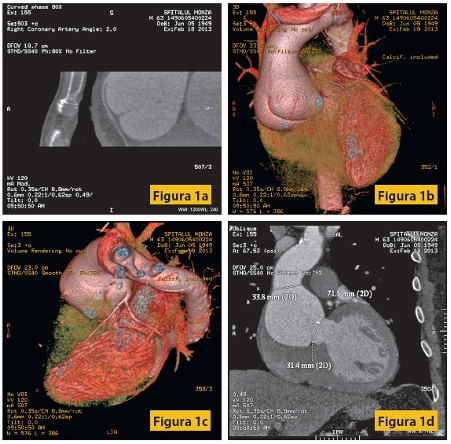

Figura1: Pacient M, 63 ani, cunoscut cu anevrism gigant de aortă ascendentă toracală, cu insuficienţă aortică severă, insuficienţă ventriculară stângă de repaus, HTA şi dislipidemie. Examinarea angiocoronaro-CT evidenţiază dilataţie anevrismală importantă a aortei ascendente, inclusiv a rădăcinii aortice, circulaţie coronariană cu dominanţă stânga, cu aspect hipoplazic al arterei coronare drepte. Fără stenoze semnificative la nivel coronarian.